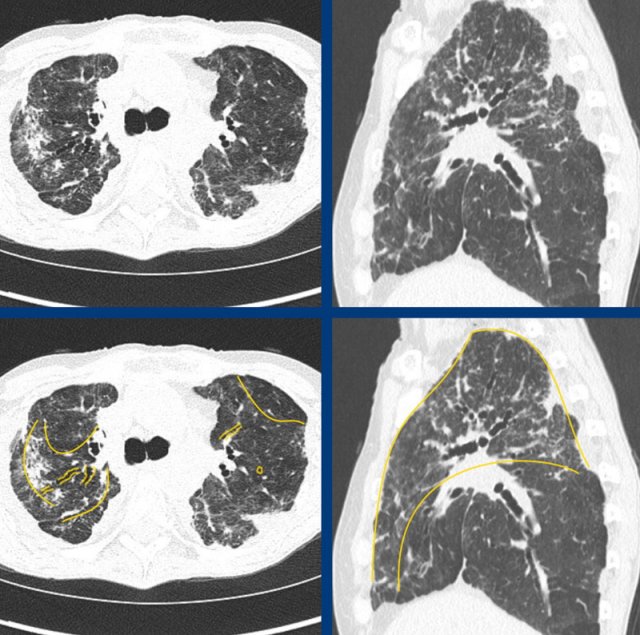

The images show fibrotic lung disease with distortion of the secondary lobule, volume loss and traction bronchiectasis (green is normal, yellow is abnormal).